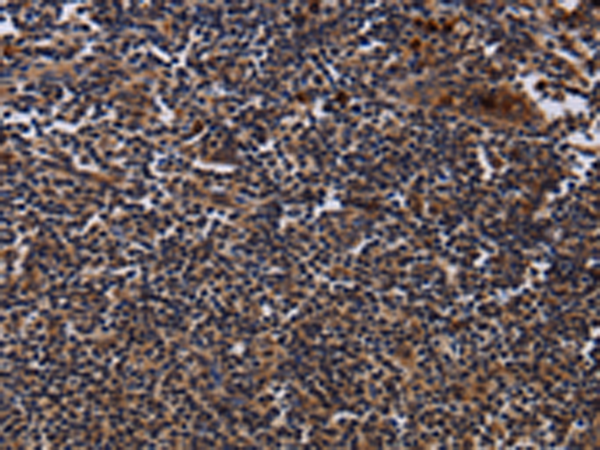

分类: 科研抗体货号: P08490别名: JTK8; p53Lyn; p56Lyn应用: IHC反应种属: Human, Mouse, Rat